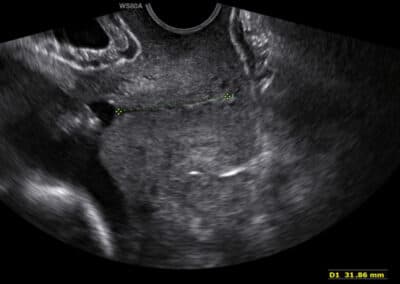

Protokol pro správné vyšetření NT:

CRL 45-84 mm (11-13+6 týden) Přesná mid-sagitální rovina (echogenní špička nosu a patro vpředu, diencefalon v centru mozku a nuchální translucence vzadu, nesmí být vidět processus frontalis maxillae) Neutrální pozice Dostatečné zvětšení (hlava a hrudník plodu vyplňují většinu obrazovky) Snížení gainu při zvětšení Odlišení hranice NT od amnion Měření v místě nejvyšší hodnoty NT Umístění značek při měření uvnitř echogenních linek ohraničujících NT na jejich hranici s tekutinou Možnost využití polo-automatických softwarů na měření NT V přibližně 5% případů je pupečník okolo krku plodu a falešně zvyšuje hodnotu NT. V těchto případech je třeba změřit hodnotu NT nad a pod pupečníkem a použít pro kalkulaci rizika průměrnou hodnotu z obou měření Provést více měření, snímek s nejvyšší hodnotou zálohovat